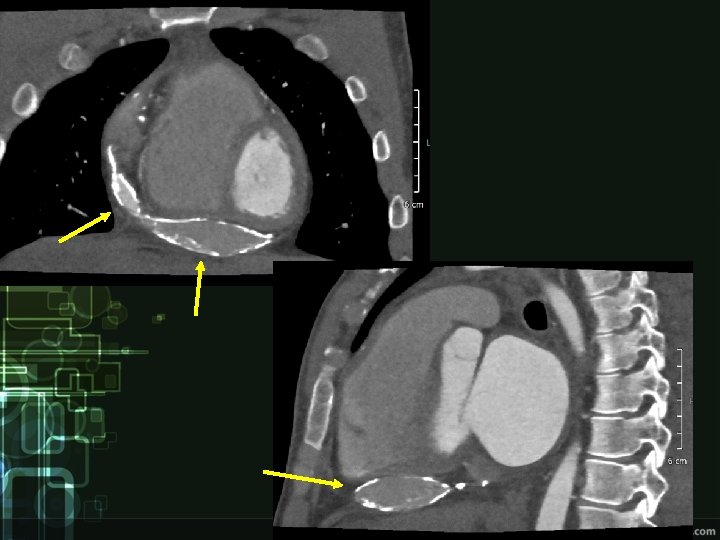

Diagnostics • Clinical picture • ECG – low voltage, repolarization changes (inverted T waves) • ECHO – thickened pericardium, impaired ventricular filling, „dancing septum“, IVC and atrial dilatation • Other imaging techniques